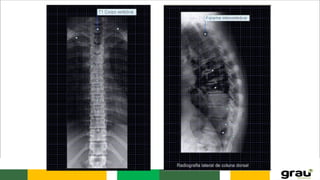

Coluna Vertebral

CURVATURAS: Primárias e secundarias

IMPORTÂNCIA CLINICA: hipercifose, hiperlordose escoliose

IMAGEM PANORÂMICA DA COLUNA !

COLUNA VERTEBRAL CURVATURAS: Primáriase secundarias IMPORTÂNCIA CLINICA: hipercifose, hiperlordose escoliose Caracteristicas das vértebras permitem identificar a que região pertencem.